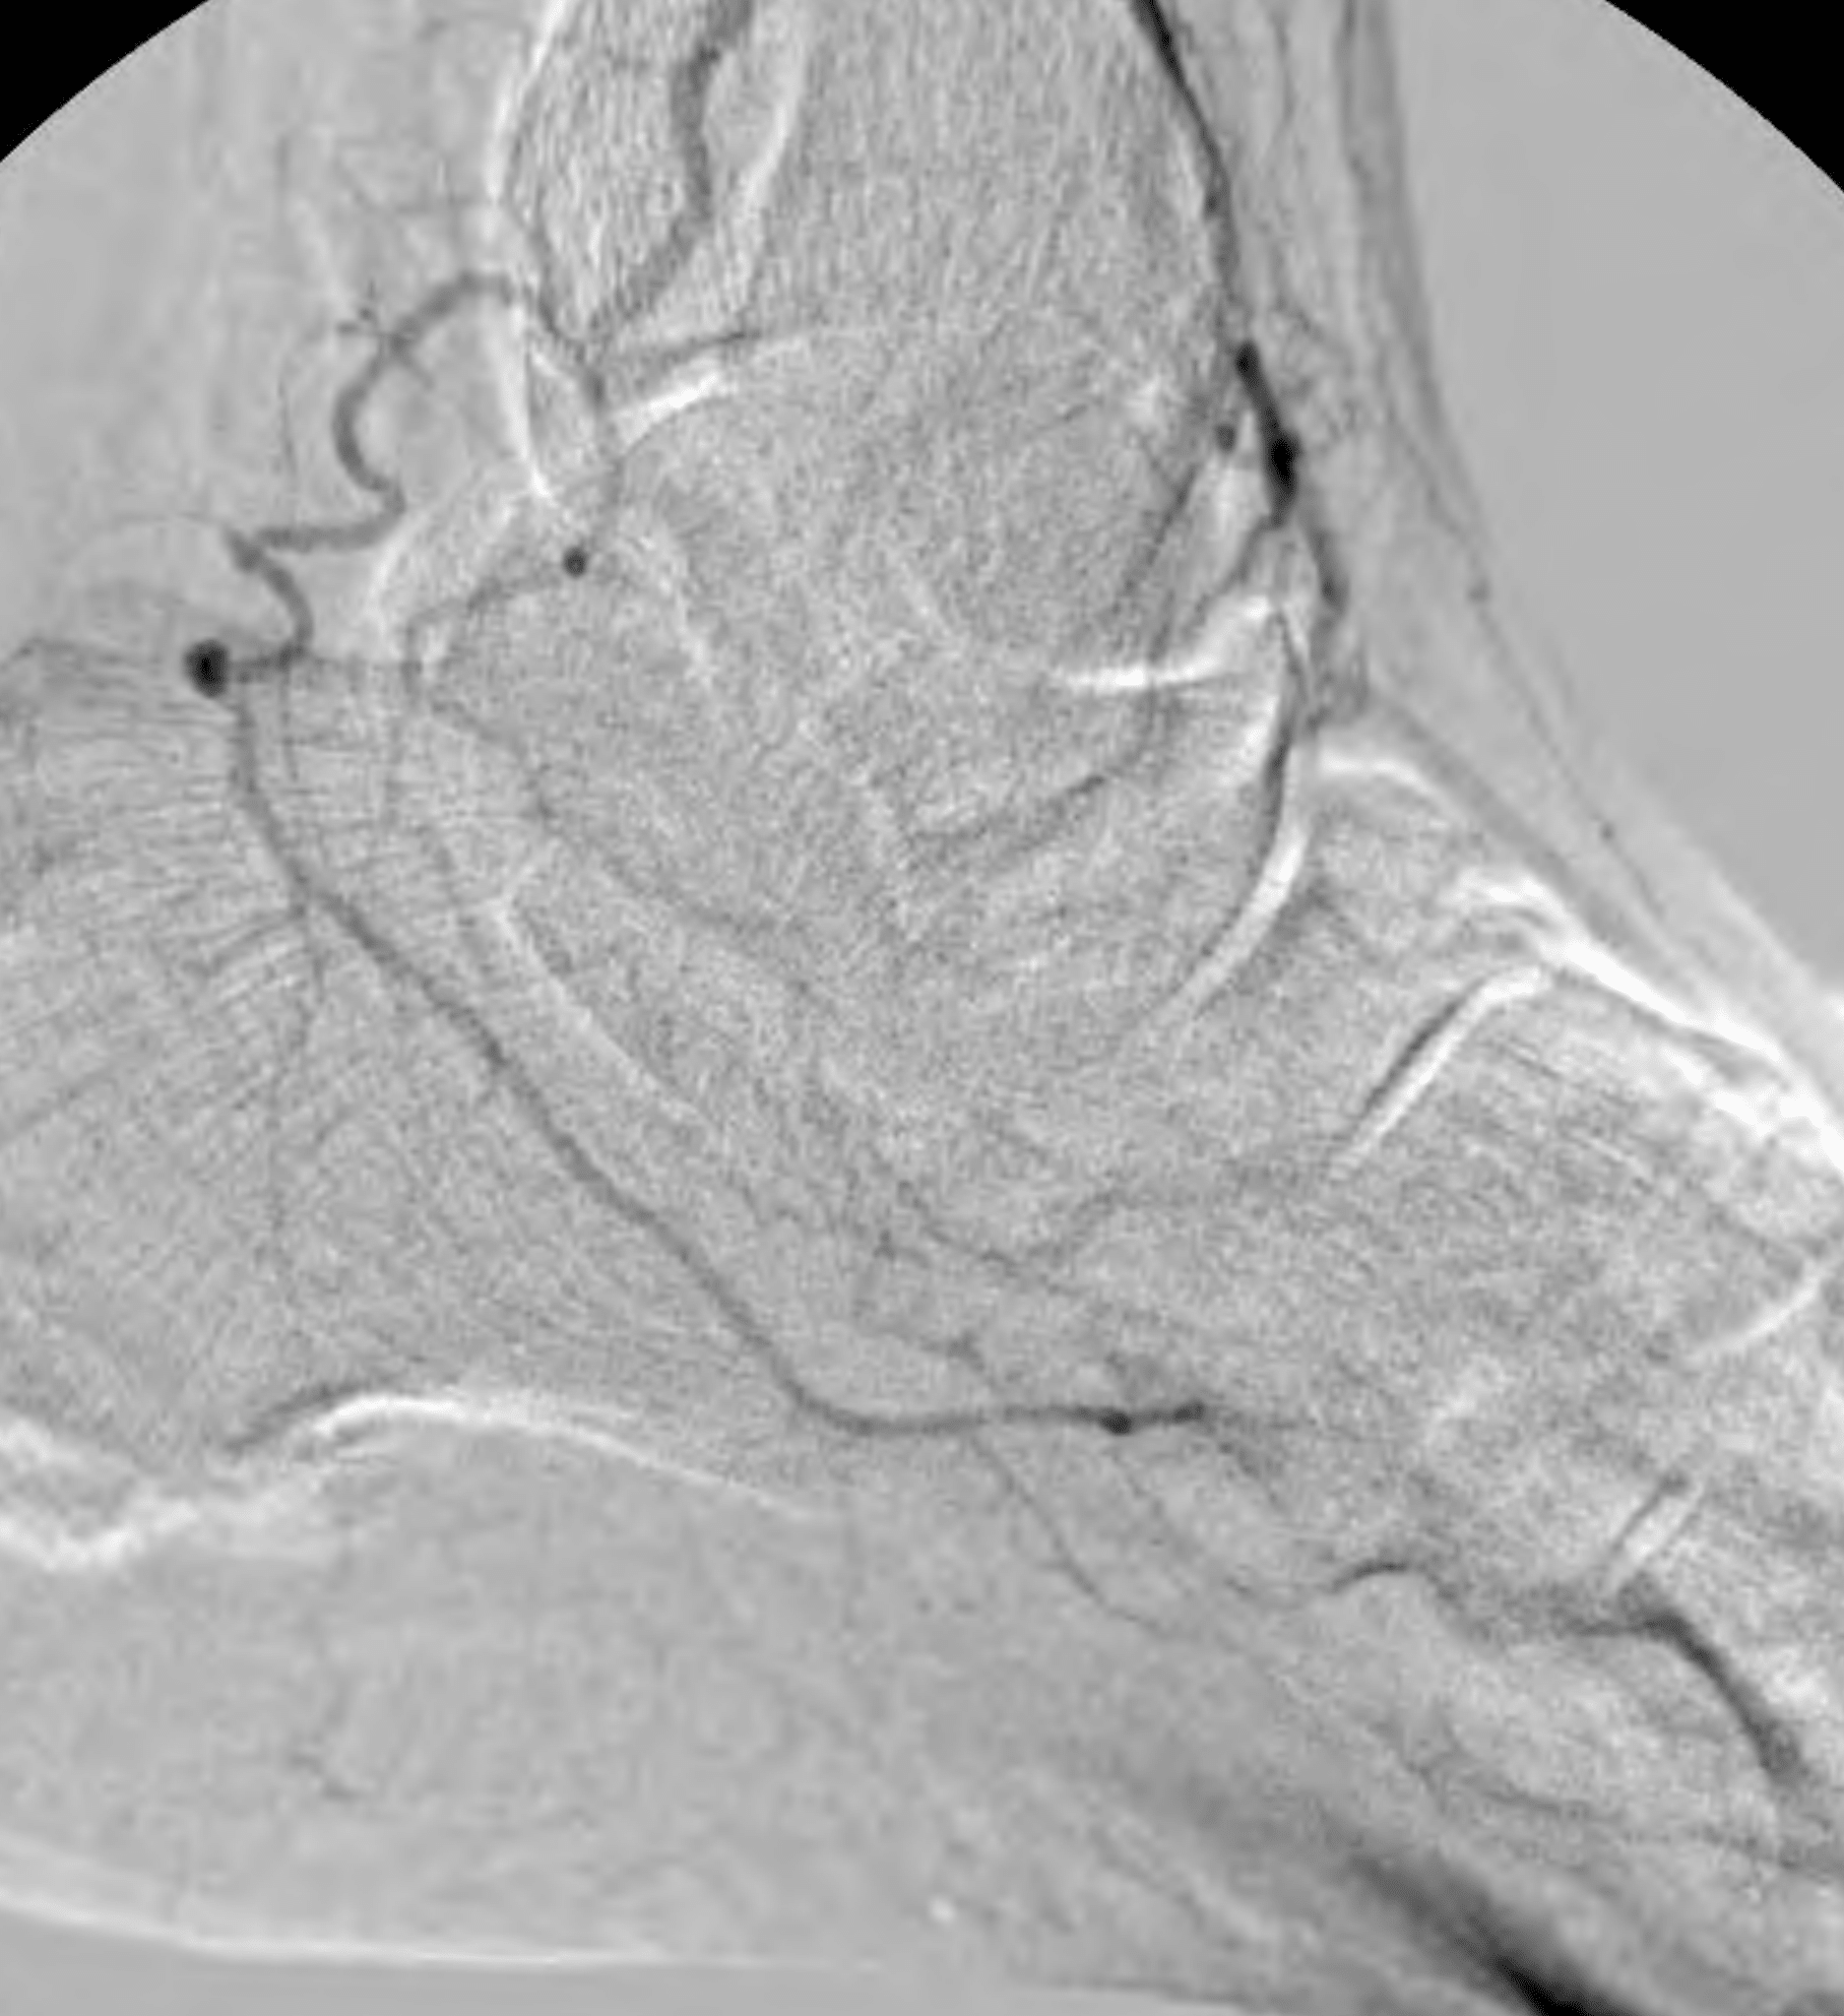

After being medically optimized, the patient was scheduled for an angiogram. The angiogram revealed occlusion of the anterior and posterior tibial arteries with reconstitution of the plantar arteries via the peroneal artery as well as reconstitution of the dorsalis pedis artery via the peroneal artery (Figures 2, 3, and 4).

The anterior tibial artery was chosen as the target of revascularization given the predominant supply to the forefoot via the dorsalis pedis artery compared with the lesser supply via the diminutive plantar arteries. An “up and over” approach from a contralateral right common femoral artery access was successful in crossing to the distal segment of the anterior tibial artery in antegrade fashion; however, further crossing could not be achieved in antegrade fashion (Figure 5).

In order to cross and treat the remainder of the distal anterior tibial artery occlusion, a retrograde pedal access was desired. Due to concerns about puncture-related injury to the dorsalis pedis artery that could potentially compromise the patient’s existing flow as well as a potential surgical bypass target, retrograde pedal access of the patent dorsalis pedis artery was avoided at this point. Instead, a plan was made to obtain retrograde pedal access of the occluded segment of the distal anterior tibial artery above the reconstitution point (Figure 6).